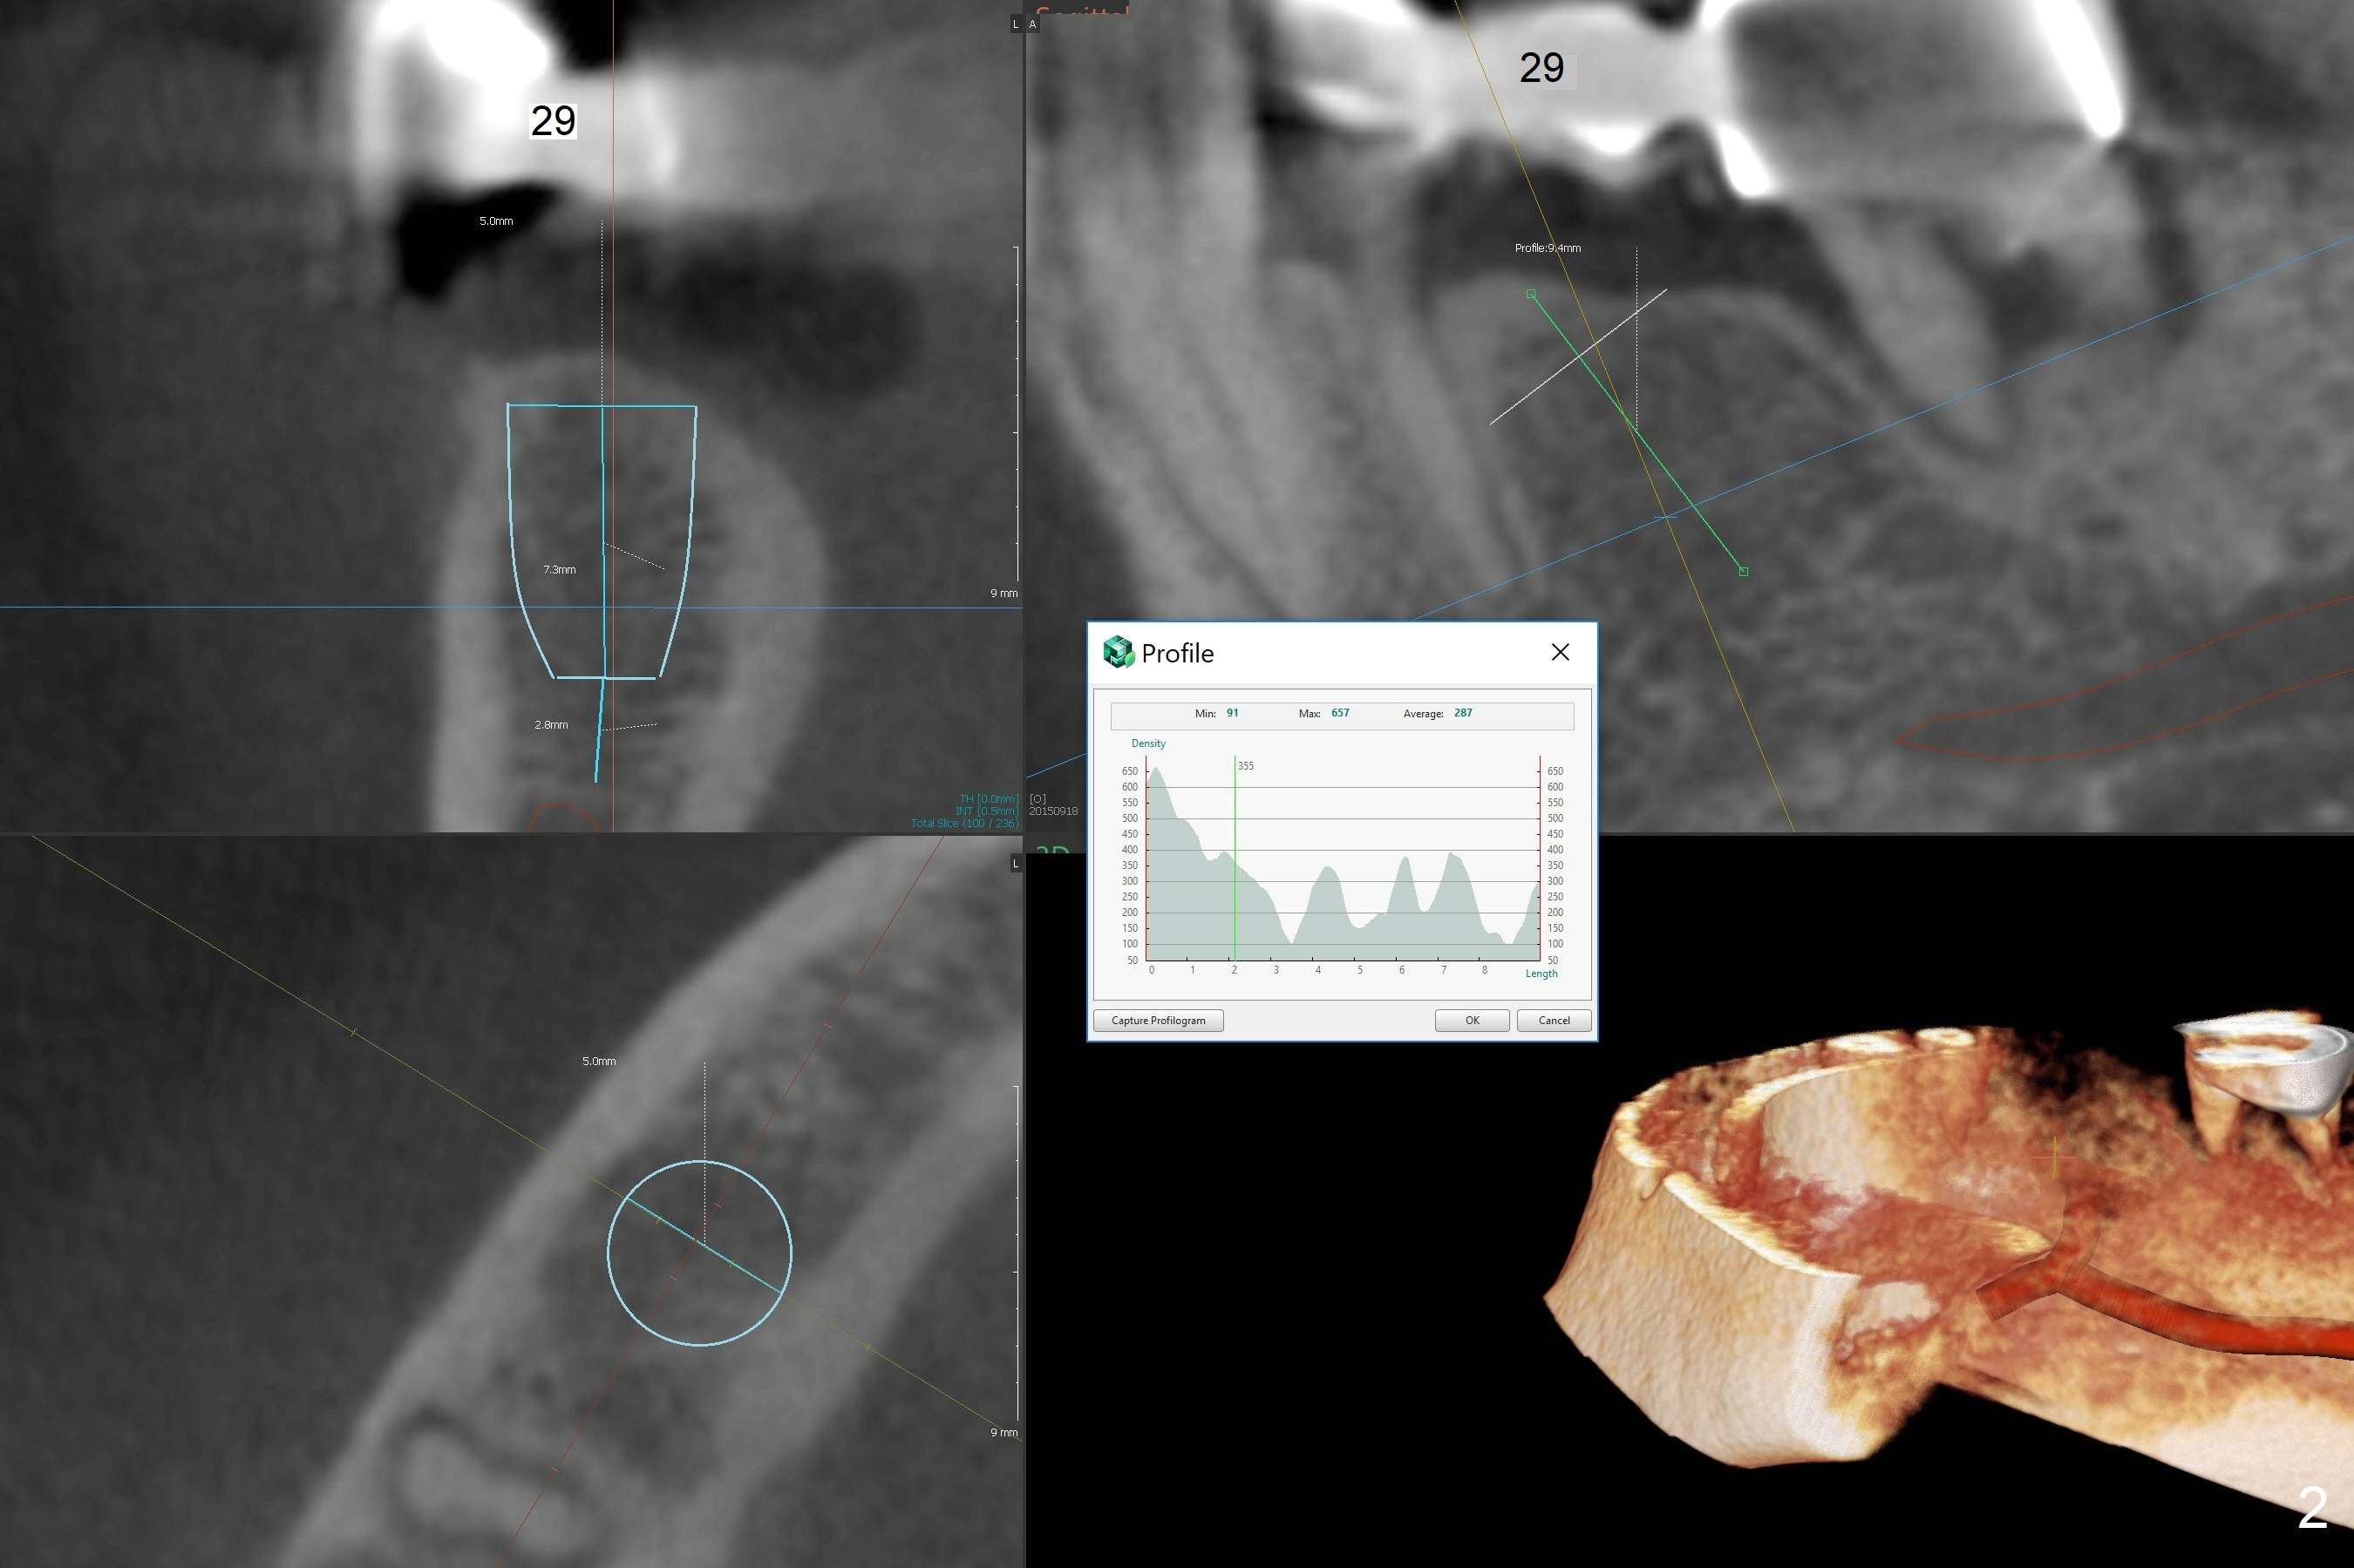

7.3 mm long Implant

A 54-year-old man has pain at #30 (Fig.1). With severe loss of bone, the tooth is non-salvageable. Section FPD between #28 and 29 before extraction of #30. Because of limited bone, 4.5x7.3 and 5x7.3 mm implants appear to be appropriate at #29 (Fig.2) and 30. Due to low bone density at #29 (Fig.2), under drilling is required.